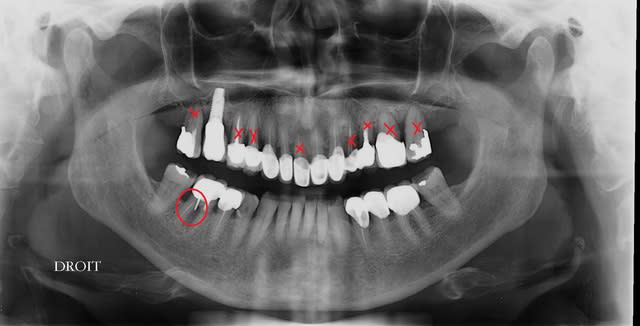

j'ai mis en rouge toutes les zones très malades, voir suceptibles d’être en fin de vie...

une radio d'implant, pas terrible mais peut être suffisante pour toi Pluton?

26,27,17,24 m'ont l'air foutues, 11 peut-etre aussi. Mobilites?

il te reste donc 1 canine et 3 incisives, plus l'implant...